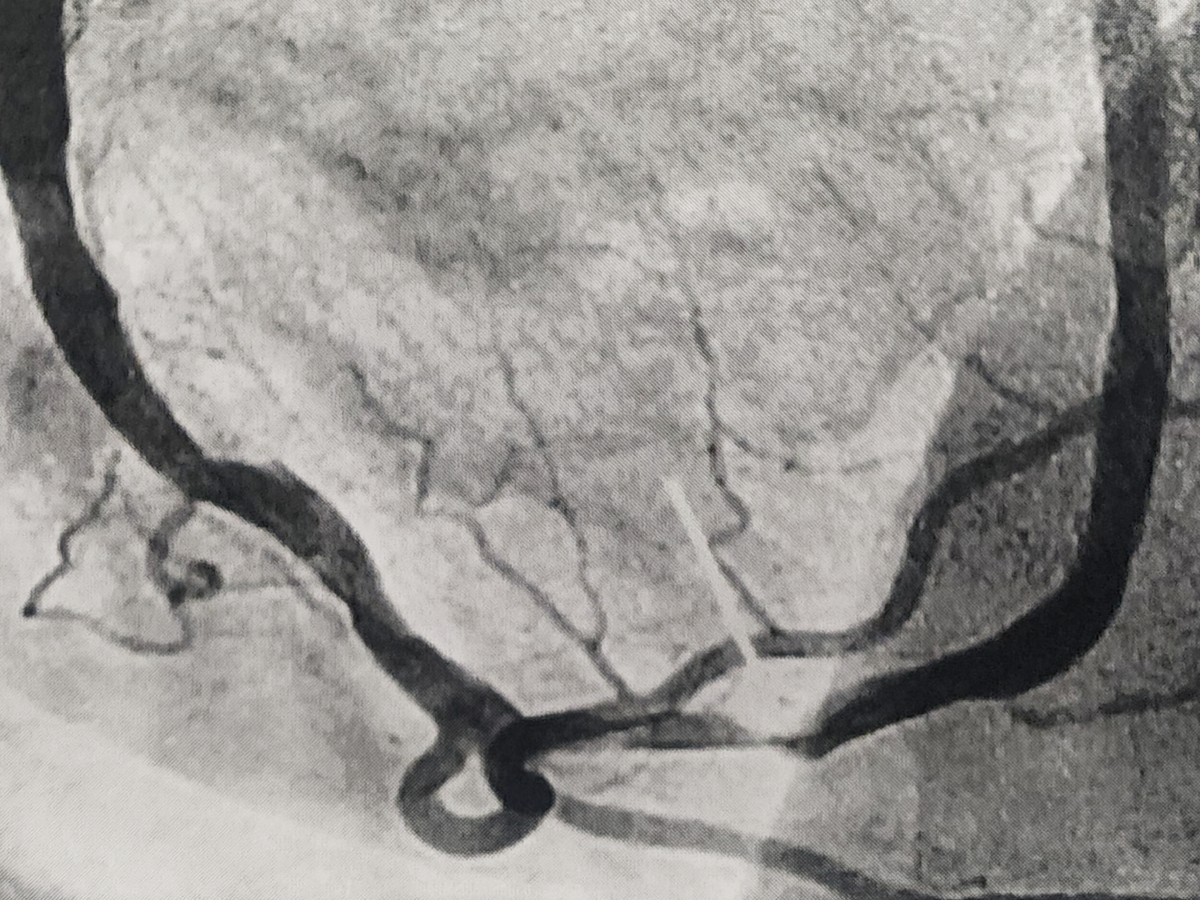

This man walked off what he knows now were possibly 3 heart attacks before the 4th had me stuffing him in the car and feeding him aspirin on the way to the hospital. This one lasted from the time he told me something wasn't right until almost 2 hours later when the surgeon in the cath lab put his 2 stents in. He can't lift more than a gallon of milk until the doctor clears him.